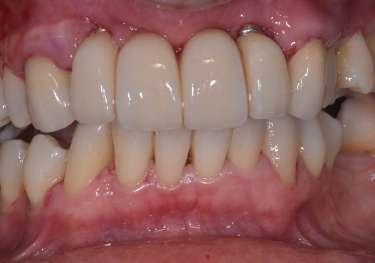

Le innovazioni tecnologiche per l’efficace mantenimento delle riabilitazioni implantari

La prevenzione terziaria è una vera sfida per l’igienista dentale, che per competenza del suo profilo professionale ha la gestione del mantenimento delle riabilitazioni odontoiatriche.

Le terapie riabilitative implantari per pazienti con edentulia parziale o totale, permettono di riportare sia la funzionalità che l’estetica, con una prevedibilità di successo che dipende, oltre che dall’efficace piano terapeutico chirurgico implantare del professionista chirurgo, anche dalla responsabilità attiva del paziente a seguire corretti stili di vita di igiene orale domiciliare e follow-up. Questi devono prevedere la visita diagnostica di controllo dell’implantologo e la visita di controllo dell’igienista dentale. Per sollecitare l’aderence ai follow-up, usare l'automazione workflow e moduli di anamnesi personalizzati (gestionale Alfa Docs) permette una migliore gestione e un monitoraggio efficace delle cure e dei richiami personalizzati in base ai bisogni extra clinici dei pazienti. La vera sfida è il management di igiene orale in pazienti presi in carico che sono stati sottoposti a terapie implantari in altri studi, e che mostrano clinicamente mucosite, con interessamento della mucosa perimplantare o con perimplantite che coinvolge l’osso di sostegno.

Spesso si evidenzia il collare implantare degli abutment, e prima che l’implantologo preveda intervento mucogengivale è fondamentale condividere con il paziente la necessità di eliminare l’infiammazione eseguendo un'igiene orale domiciliare attenta ed efficace. L'igiene orale domiciliare deve essere considerata terapia.

biofilm batterico domiciliare. Per il controllo meccanico del biofilm batterico, se viene lamentata dolorabilità, si deve concordare l'uso di uno spazzolino con setole che siano efficaci ma che non creino dolorabilità durante l’utilizzo (GUM Sonic Sensitive).

(olio extravergine di oliva ozonizzato, acido ialuronico, aloe vera, cetilpiridinio cloruro, ratania) accelera il processo di guarigione, riduce la risposta infiammatoria e l'edema (sciacquo è di 1 minuto ripetuta fino a due volte al giorno). La terapia parodontale non chirurgica è fondamentale per i follow-up a medio e lungo termine per il paziente con riabilitazione implantare.

Bisogna accertarsi che non sia presente pus, sintomo predittivo di perimplantite e probabile perdita ossea, che va valutata dall’implantologo radiograficamente, con particolare attenzione alla perdita ossea interprossimale. Se presente, è importante l’approccio motivazionale di concordance con la persona assistita per responsabilizzarlo al controllo del biofilm batterico degli spazi interprossimali

Successivamente alla diagnosi ricevuta dall’implantologo e le indicazioni sul piano terapeutico scelto, capita spesso di intervenire con una terapia di supporto palliativa, che ha l’obbiettivo di mantenere le condizioni della riabilitazione in buon stato clinico. L’ascolto del paziente è fondamentale per accogliere i disturbi percepiti dal paziente quali disestesia, sensazione di corpo estraneo o dolore.

L’utilizzo degli scovolini in gomma, (GUM Soft Picks Confort Flex), risultano essere delicati sui tessuti perimplantari, ed efficaci, grazie alle differenti misure possibili, per la personalizzazione della scelta dell’interprossimale a seconda dello spazio sovracrestale.

L’evoluzione di tecnologie così sofisticate ha permesso di poter offrire l’opportunità di fare “la giusta scelta” personalizzata per ogni caratteristica anatomica, di maualità e predisposizione di fragilità, o soltanto seguire l’approccio caratteriale del paziente.

(TBM) Nardi G.M. et al. Tailored Brushing Method (TBM): an innovative simple protocol to improve the oral care. J Biomed 2016; 1:26-31. Il protocollo di igiene orale deve essere personalizzato in base alla tipologia del manufatto protesico implantare, poiché spesso la persona assistita ha difficoltà di efficacia nel controllo del

Per il controllo chimico del biofilm batterico domiciliare, l’olio di oliva ozonizzato è molto apprezzato dalla persona assistita poiché ha un gusto gradevole, non crea discromie sulle superfici dentali e implantari e può essere usato quotidianamente, aspetti che non vanno trascurati poiché permettono compliance e maggiore aderence alle terapie di igiene orale domiciliare.

L’uso del colluttorio all’olio di oliva ozonizzato Ialozon Blu (GEMAVIP),

L’ aMMP-8 (metalloproteinasi di matrice attiva) è un biomarker per la diagnosi precoce di malattie gengivali, processi degenerativi dei tessuti molli e duri a livello parodontale e perimplantare. La presenza di aMMP-8 si riscontra prima di qualsiasi segnale di infiammazione o perdita di tessuto. Dalla valutazione di efficacia della terapia parodontale non chirurgica coadiuvata dall’utilizzo di collutorio a base di olio ozonizzato, sui valori oggettivi di Metalloproteasi salivare (MMP-8) nel paziente affetto da parodontite, è stato evidenziato che lo SRP coadiuvato dall'utilizzo domiciliare di collutorio a base di olio ozonizzato contribuisce ad un più accentuato miglioramento dei parametri clinici parodontali Nardi GM, Cesarano F, Papa G, Chiavistelli L, Ardan R, Jedlinski M, Mazur M, Grassi R, Grassi FR. Evaluation of Salivary Matrix Metalloproteinase (MMP-8) in Periodontal Patients Undergoing Non-Surgical Periodontal Therapy and Mouthwash

Based on Ozonated Olive Oil: A Randomized Clinical Trial. Int J Environ Res Public Health. 2020 Sep 11;17(18):6619. doi: 10.3390/ijerph17186619. PMID:32932898; PMCID: PMC7558934. IF:3,390, Evidenze scientifiche hanno dimostrato che gli ozonidi selezionano la crescita di un microbiota più favorevole all’eubiosi del cavo orale limitando la proliferazione di microrganismi opportunistici.

L’uso di ablatori che permettano in maniera ergonomica di erogare deplaquing e debridment con la possibilità di scelta di differenti punte per un migliore adattamento alla superficie sono ideali per una terapia parodontale non chirurgica efficiente, ed un timing operativo agevole per l’ope-

10 www.infomedixodontoiatria.it

ratore e per il paziente (Combi Touch Mectron). Il sondaggio parodontale permette la diagnosi della malattia perimplantare e va eseguito con una sonda in materiale plastico con delicatezza ed una forza controllata di 0.25 N, per evitare danni alla mucosa perimplantare. In caso la sonda evidenzi una tasca perimplantare, può essere usato il gel Perioral 3 (GEMAVIP) all’olio di oliva ozonizzato.

Nei pazienti che dimostrano inefficacia nell’igiene domiciliare per le difficoltà oggettive della riabilitazione protesica, oltre che l’uso del coluttorio Ialozon Blu ad uso quotidiano, si può ricorrere alla terapia fotodinamica domiciliare. Il nuovo dispositivo Lumoral (Koite Health) permette un trattamento antinfiammatorio nei casi di prevenzione terziaria, e quindi opportuno nei pazienti implantari. La PDT basato su ICG è efficace e controlla la quantità di agenti patogeni orali, con una crescita batterica compensata in specie associate a una buona salute orale, ma senza un cambiamento nella diversità batterica complessiva. Il trattamento domiciliare del Lumoral ha un effetto antinfiammatorio e può prevenire lo sviluppo della mucosite. Dopo la riabilitazione implantare la persona assistita potrà applicare il Lumoral per 10 minuti, 2 volte la settimana, dopo aver

sciolto in acqua una compressa di Lumorinse ed aver fatto sciacquo per 60 secondi con la soluzione. Questa aderirà al biofilm batterico e la luce del Lumoral la attiverà. Successivamente alla applicazione fotodinamica, personalizzata nei tempi in base alla condizione clinica presente, il paziente potrà continuare con la sua igiene orale domiciliare.

Il fumo influenza le alterazioni ossee marginali perimplantari aumentando il rischio di un significativo aumento della perdita ossea marginale L’obiettivo da perseguire nella gestione del paziente fumatore è la sospensione totale del fumo, ma nel caso di resistenza alla disassuefazione, efficace se affidata ai centri antifumo del Servizio Sanitario Nazionale, per contenere il rischio e ridurre l’esposizione alle sostanze tossiche generate dalla combustione del tabacco (temperatura che raggiunge dai 600°C, agli 800°C durante il tiro della sigaretta tradizionale), l’uso dei prodotti a tabacco riscaldato, seppur non

privi di rischi, riduce l’esposizione alle sostanze tossiche generate dalla combustione

Il successo della terapia implantare è determinato dal controllo della stabilità, dall’approccio clinico di prevenzione efficiente, dalla scelta di tecnologie che permettano il coinvolgimento at-

tivo della persona assistita a medio e lungo termine

I follow-up sono indispensabili per intercettare segni clinici di infiammazione e per coinvolgere il paziente ad un auspicabile stato di eubiosi del cavo orale, rendendolo consapevole della multifattorietà della perimplantite data dalla presenza di biofilm batterico, dalla genetica, da stili di vita voluttuari come il fumo, dalla presenza di eventuali malattie sistemiche, dalla tipologia della riabilitazione protesica, da eventuale pregressa diagnosi di malattia parodontale.